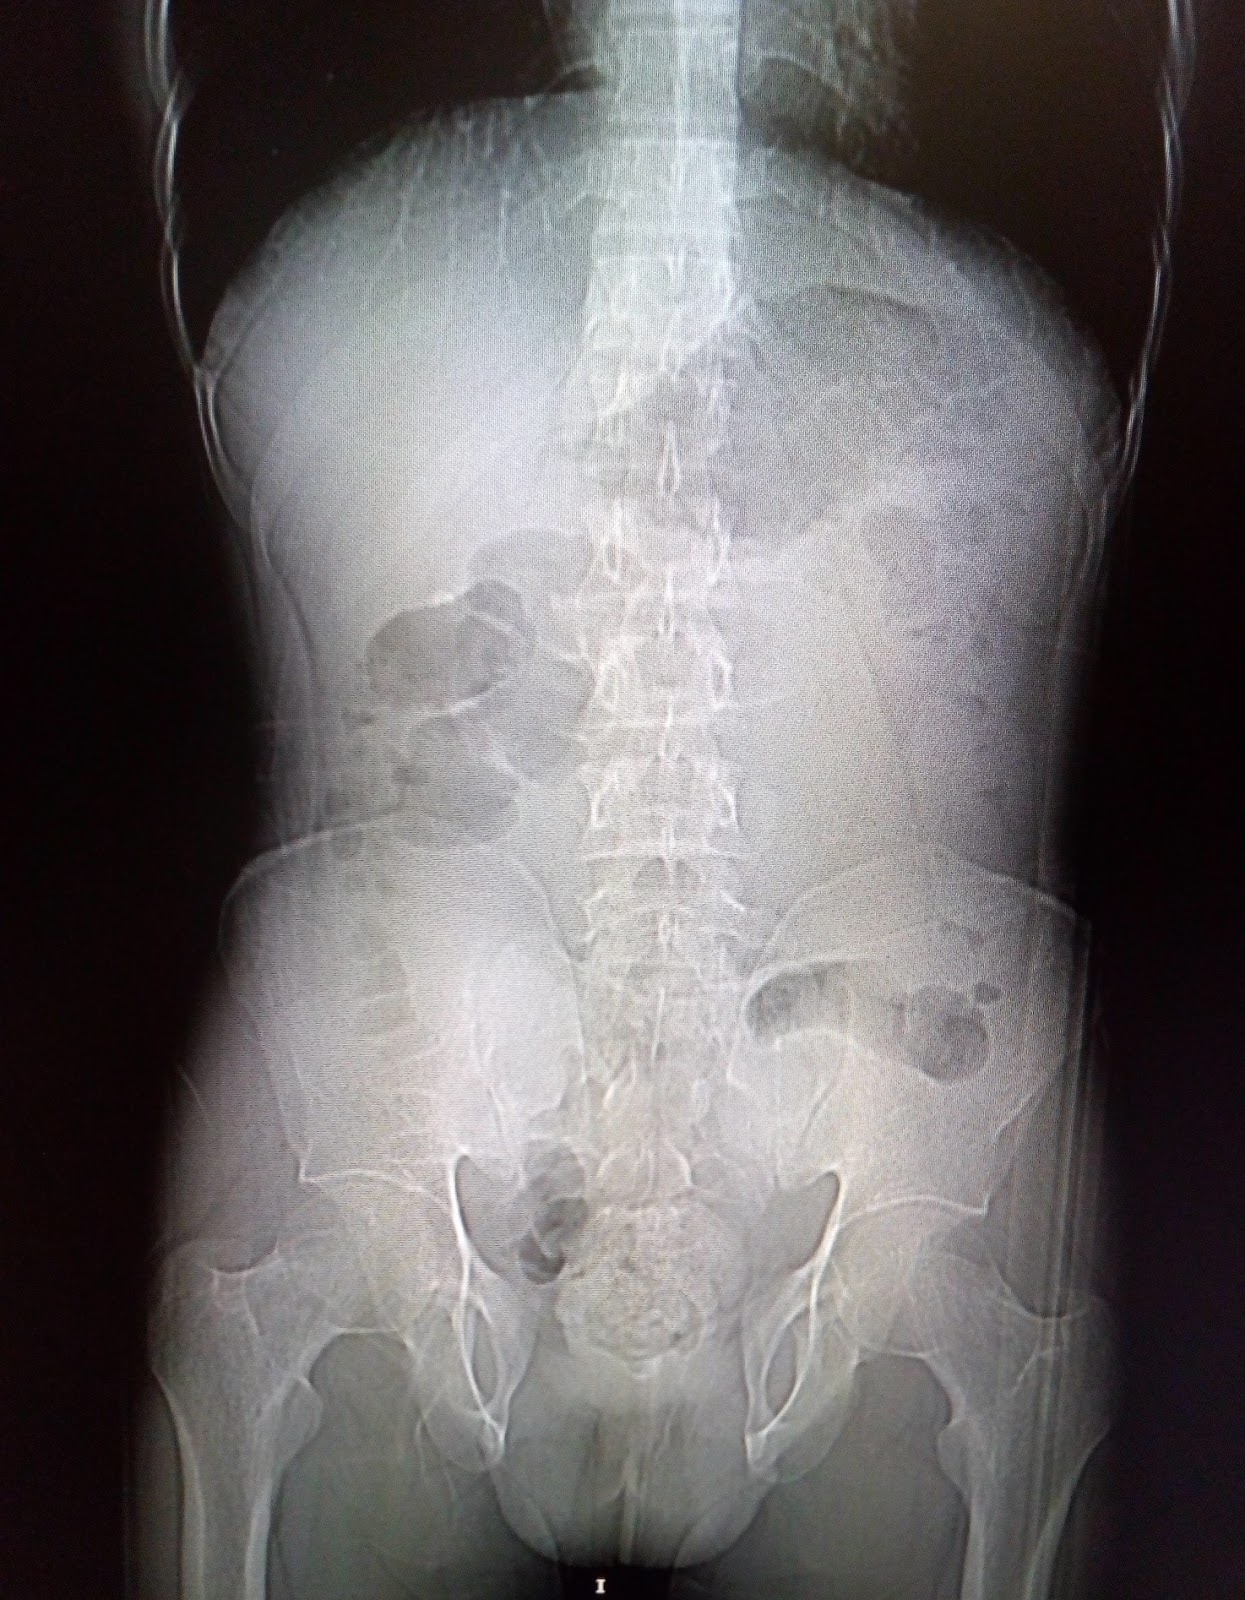

Exstrophy of the urinary bladder is a very rare congenital deformity in which the anterior bladder wall is absent and the posterior wall of the bladder is exposed externally into. Bladder exstrophy is seen 1 in. Bladder exstrophy is a rare condition when a baby's bladder sticks out through the wall of the stomach (abdomen).

The disorder may occur in varying degrees and may involve other organs including the bowel, external genitalia and pelvic.

Bladder exstrophy, also known as classic bladder exstrophy, is when the defect is limited to the bladder and the urethra. In 2018, on a trip to uganda to serve children and families with exstrophy, executive director. In girls born with bladder exstrophy, the bladder is on the outside of the body and the vagina is not fully formed.

The exposed bladder cannot function normally. Surgeons will close the bladder (top right) and then close the abdomen and skin. In boys born with bladder exstrophy, the bladder is on the outside of the body and the penis and the urine tube (urethra) are not fully closed.

Our faces of be book, a photo book showcasing individuals with exstrophy from around the world, is now available for purchase! There may be a rudimentary posterior wall. Bladder exstrophy is a rare, complex congenital birth defect that involves abnormalites of multiple body systems and organs including the lower abdominal wall, bladder, pelvis, genitalia, rectum and anus.